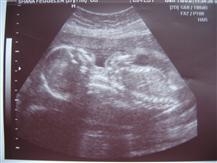

Back from my 20 Wk Ultrasound....

I'm resizing pics as I type...but I'm happy to report we are right on target with how far along I am and how big she is. They think she weighs about 10 ounces.

We reconfirmed that she is a girl and SO NOT SHY about it

She sucked her thumb, had the hiccups, and even flipped from face up to face down. We saw all sorts of different parts of her body which was amazing.

Image Attachment(s):

Your pictures always come out so perfect...like you can see every little bone. Incredible!!

it's the camera! I have a micro/macro function that allows me to take pics of small detals!